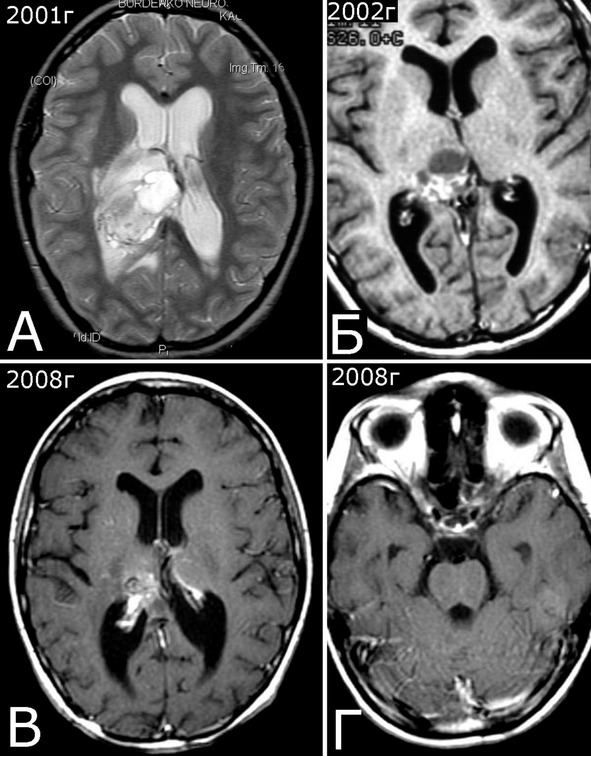

Рис. 28.III. Б-ная К-я, 1988 г. р. Радиоиндуцированная кавернозная мальформация и множественный дисангиогенез (?).

Анамнез (б-ная К-я, 1988 г. р.): в 2001 г (13 лет) обнаружена и удалена (субтотально) глиобластома задних отделов зрительного бугра справа. Проведен курс лучевой терапии. (А – МРТ до операции, режим Т2; Б – МРТ после операции и лучевой терапии, режим Т1). В августе 2002 г произведено радиохирургическое лечение оставшейся части опухоли. При последущих ежегодных обследованиях признаков продолженного роста опухоли не было (В – контрольная МРТ в 2008 г, режим Т1). Неврологического дефицита не было. С января 2011 г после падения на улице появилось пошатывание при ходьбе, которое через несколько месяцев регрессировало. При очередном контрольном обследовании в 2012 г выявлено объемное образование червя мозжечка, расцененное как хроническая гематома (Д, Е – МРТ, режимы Т2, Т1). Кроме того, в режиме SWAN обнаружено множество мелких очагов низкого сигнала, преимущественно перивентрикулярно, имеющих вид КМ IV типа (Ж, З – МРТ, режим SWAN). 01.11.2012 выполнена операция удаления гематомы: Поверхность червя мозжечка в средних его отделах резко изменена, желтого цвета и выбухает. Произведена коагуляция прилежащих участков коры и на глубине нескольких мм обнаружена капсула хронической гематомы. Капсула очень плотная. Она рассечена скальпелем. Содержимое ее – организовавшиеся кровяные сгустки. Помимо основной организовавшейся гематомы было еще несколько крупных полостей с такими же плотными стенками, заполненными кровяными сгустками. С передней части к упомянутому выше новообразованию подходили ветви мозжечковых артерий, которые коагулированы и пересечены. Основные стволы были смещены в сторону и сохранены. Постепенно путем кускования и иссечения фрагментов гематомы, по всей вероятности, и кавернозной мальформации, это новообразование удалено полностью. Оно было окружено измененной мозговой тканью желтого цвета. Ложе удаленной гематомы выложено гемостатической ватой. Образовалась больших размеров полость в пределах верхних и средних отделов червя и прилежащих отделов мозжечка. Гистологический диагноз: ткань мозжечка с капсулой гематомы с кровоизлияниями различной давности, скоплениями макрофагов и сидерофагов, очаговыми лимфоидными инфильтратами. В капсуле гематомы обнаружен микроскопический фрагмент кавернозной мальформации (Л – гистологический препарат, ув. Х 50). МРТ после операции – полное удаление гематомы (И, К – МРТ, режим Т1).